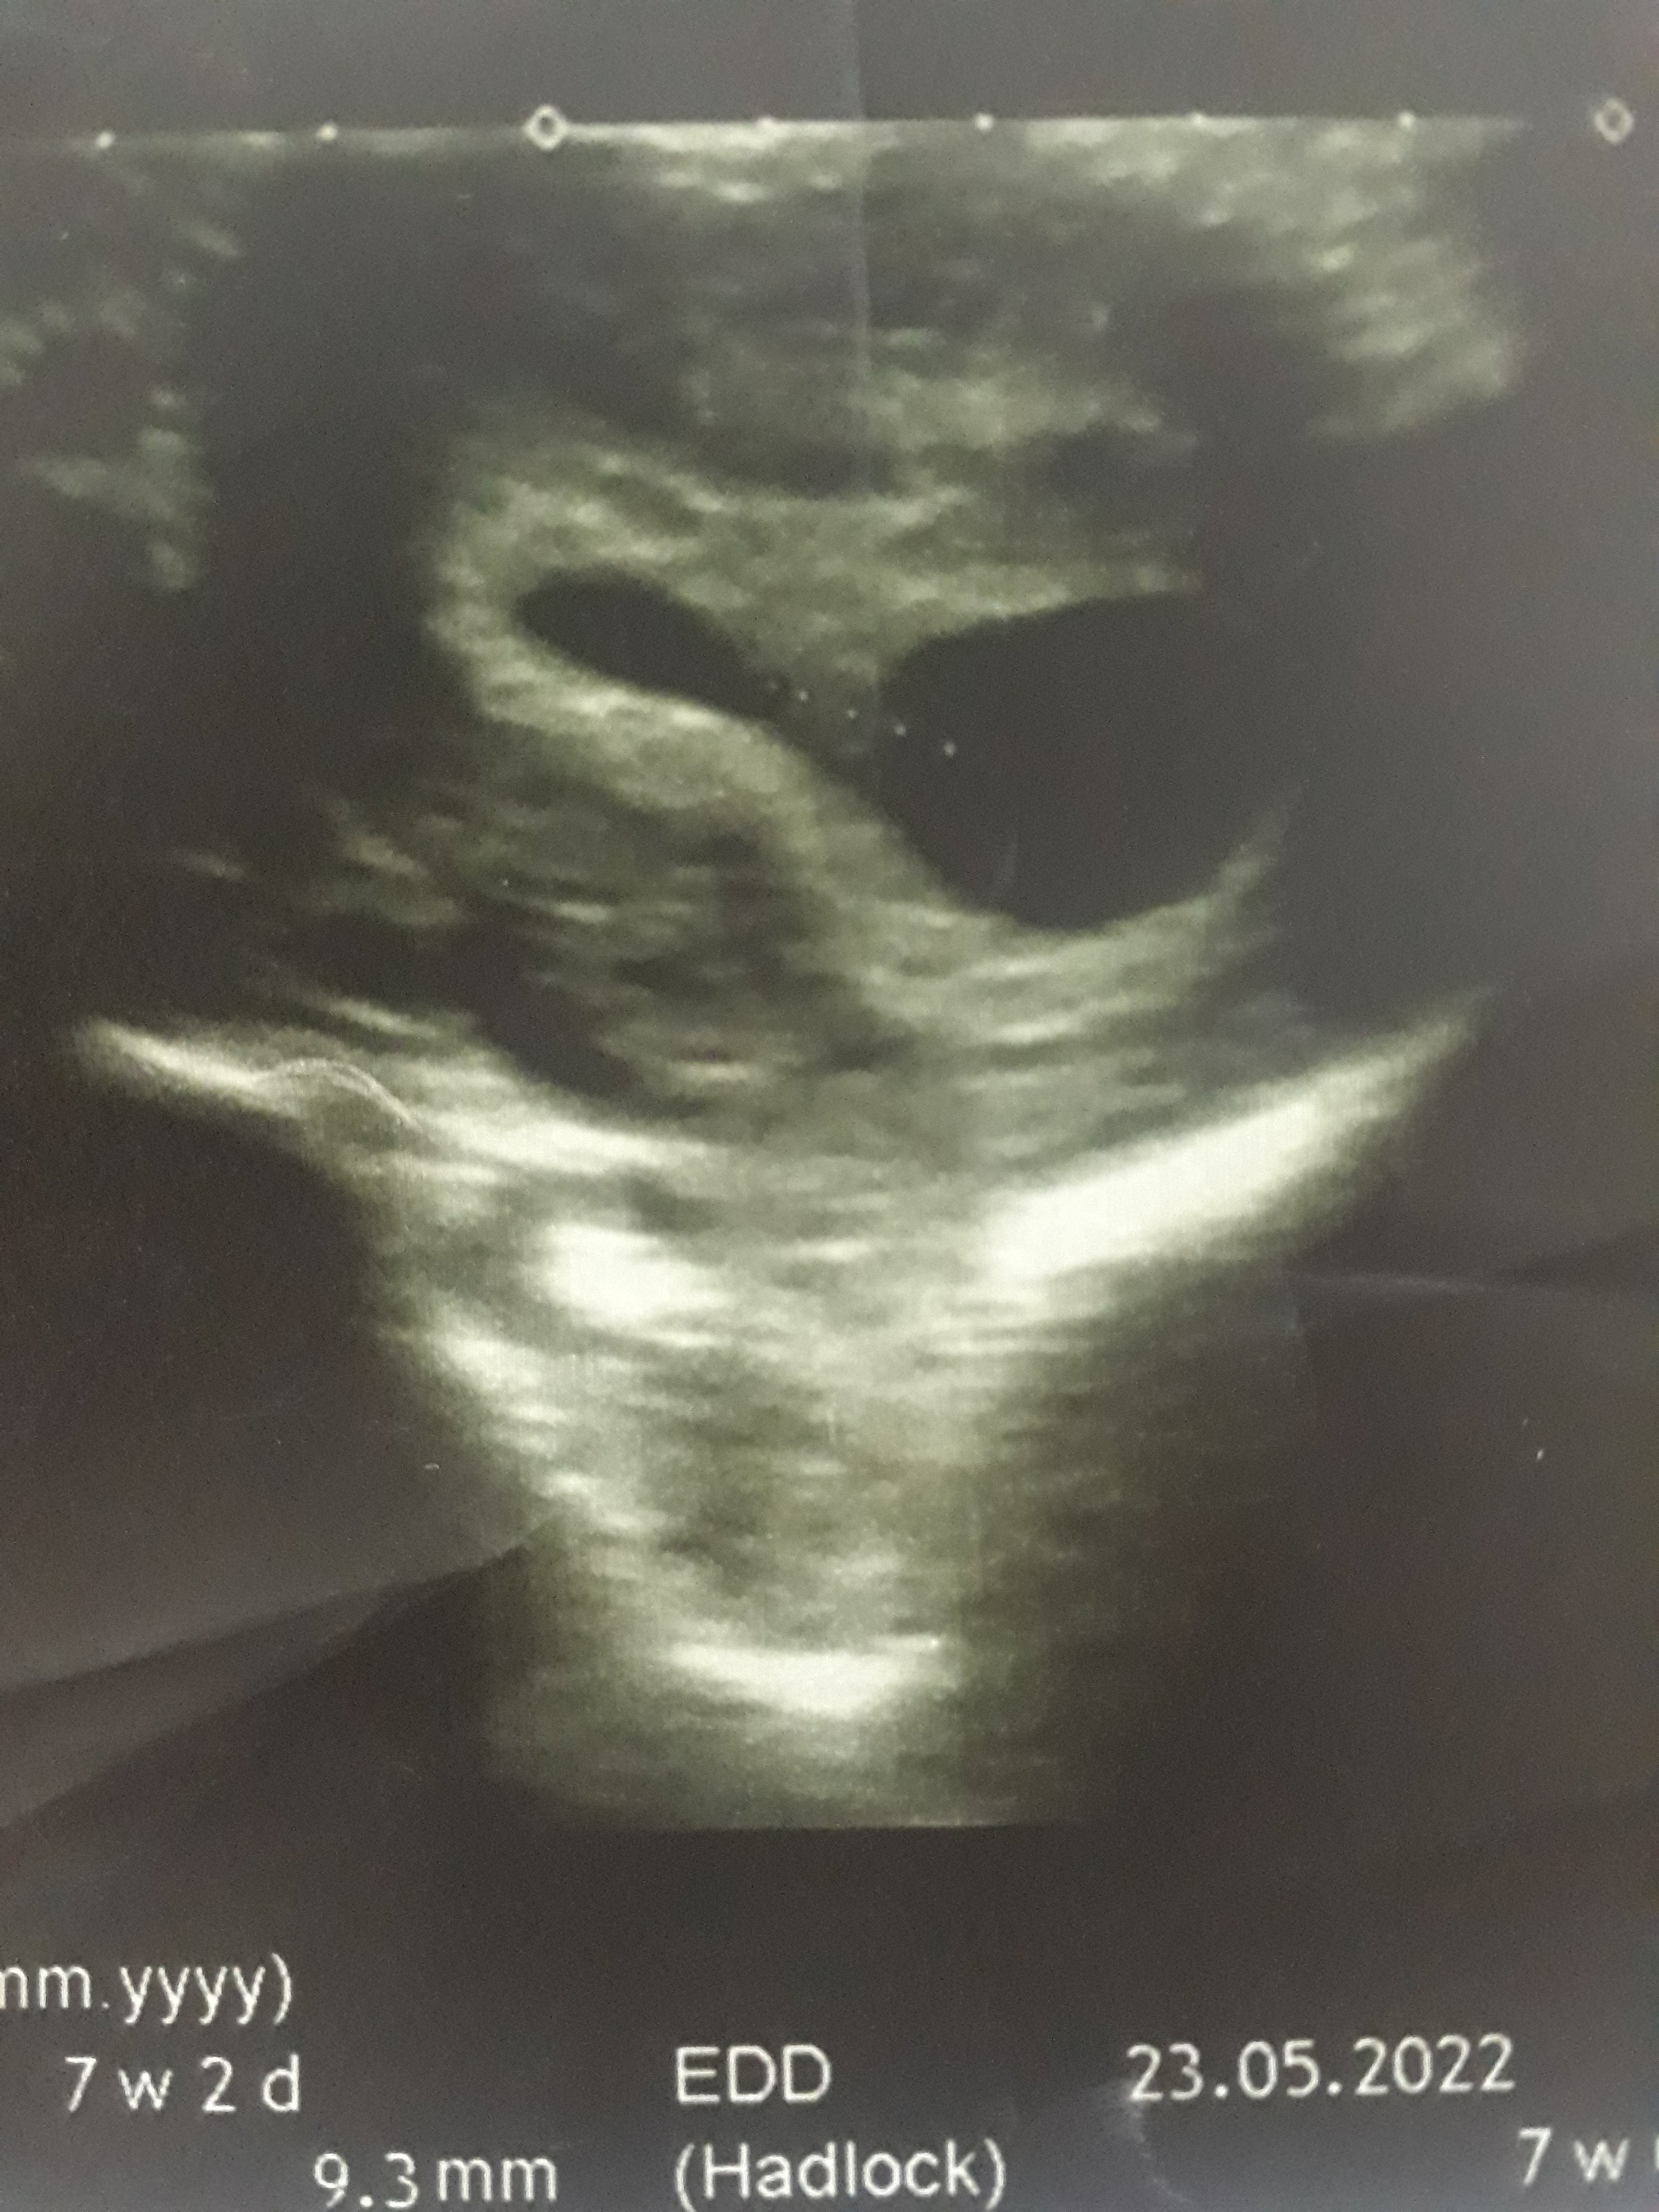

ultroson kağıdı

Konu Başlığı ultroson kağıdı

• 20211028_214147.jpg

1.6 MB · Görüntüleme: 164